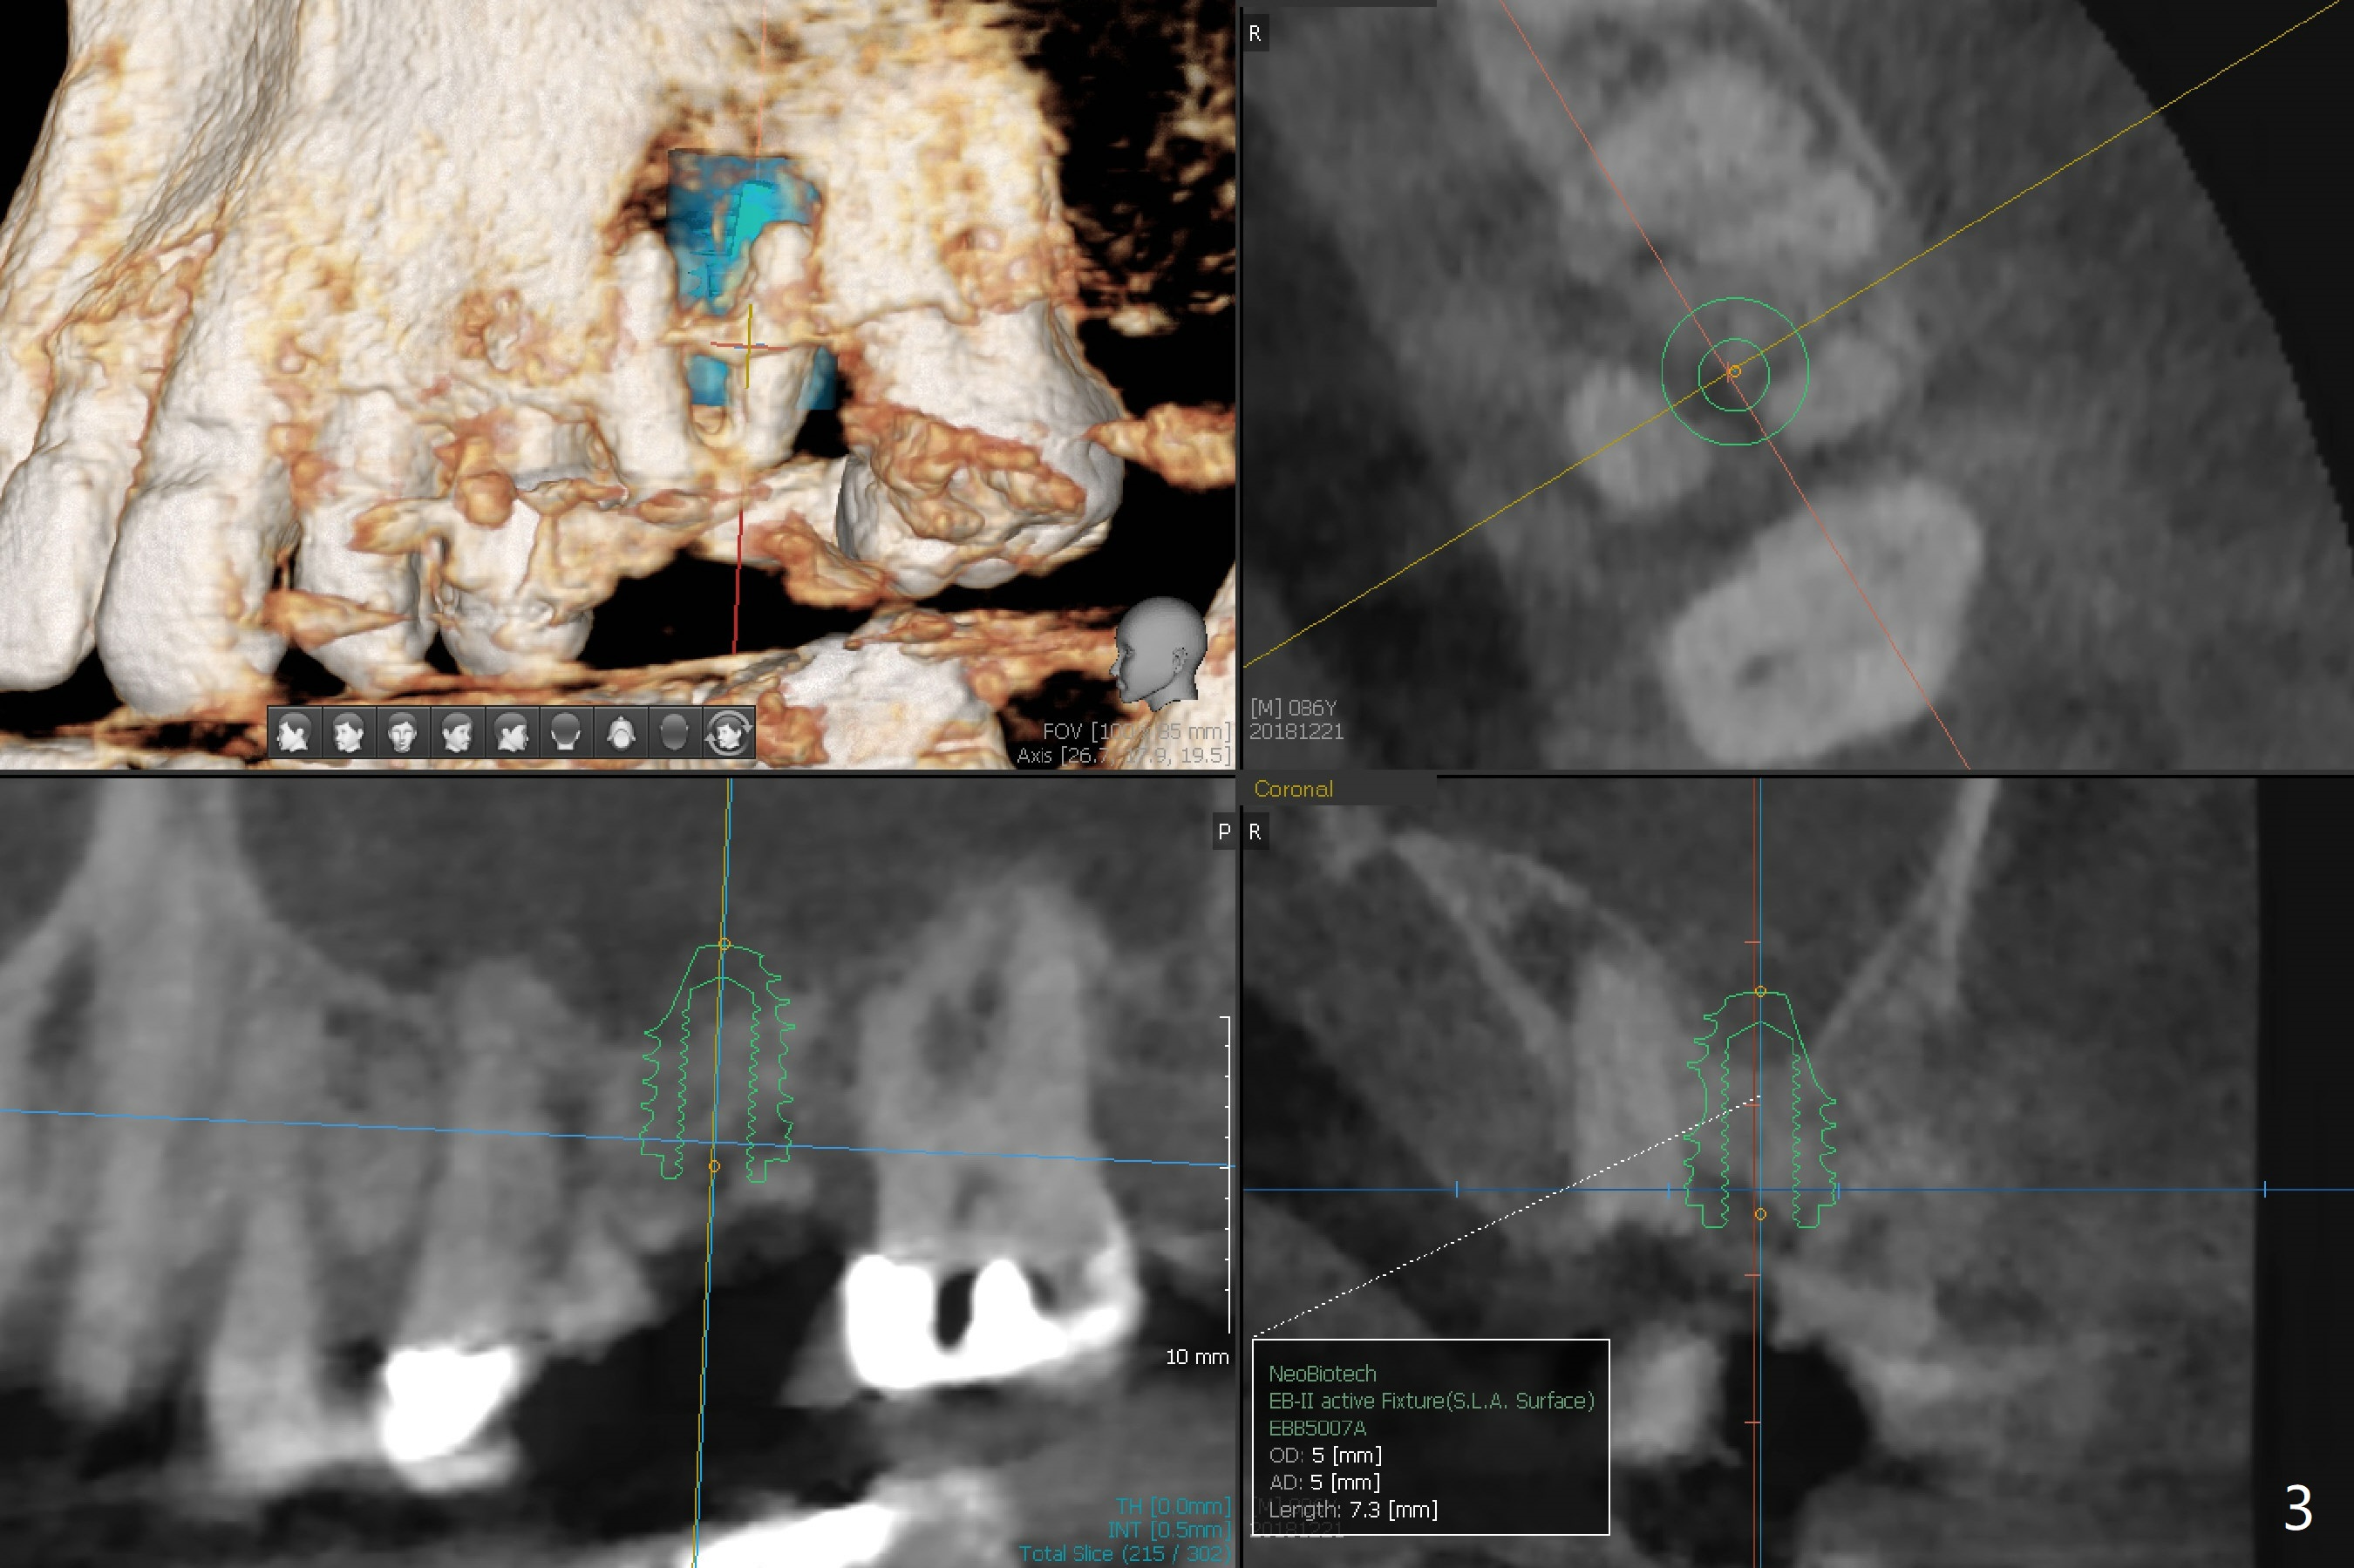

A 86-year-old man presents to clinic with chief complaint of irritating chipped tooth lower right (Fig.1 #31). Composite is placed on the condition that he should return for #14 residual root treatment (Fig.2). Since there is large periapical radiolucency and short bone height (~6 mm), should the tooth be extracted for immediate sinus lift and delayed implant or immediate implant (Fig.3)?

Return to Upper Molar Immediate Implant, Prevent Molar Periimplantitis (Protocols, Table), Trajectory, Clindamycin Metronidazole No Antibiotic Xin Wei, DDS, PhD, MS 1st edition 12/21/2018, last revision 12/26/2018